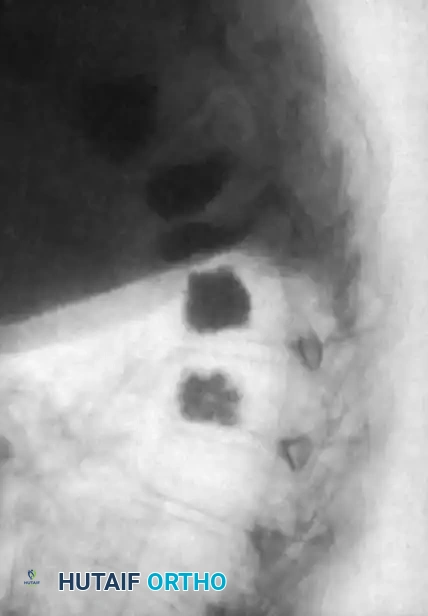

Associated Surgical & Radiographic Imaging